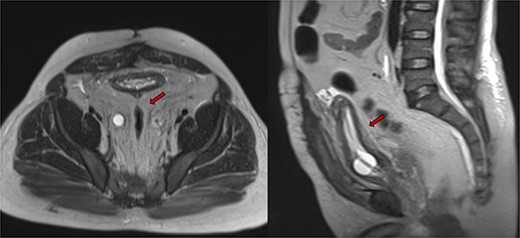

Despite initial stability, the patient’s creatinine levels rose again, and hydronephrosis worsened. Left percutaneous nephrostomy and antegrade stenting ultimately stabilized his creatinine, and he now undergoes annual stent exchanges. Follow-up abdominopelvic MRI T2WI revealed PL surrounding the urinary bladder and rectum (Fig. 2, red arrow). Additional imaging with axial and sagittal CT cystogram showed urinary bladder wall thickening (Fig. 3, yellow arrow) accompanied by extensive PL and fat stranding (blue arrows).

Abdominopelvic MRI T2WI PL surrounding urinary bladder and rectum (red arrow).